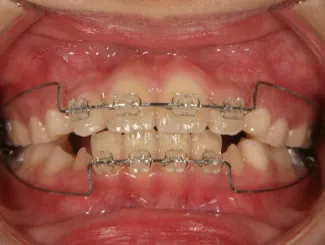

ブラケット

治療中➁小3:9y8m QH、BH、前歯並び替え終了